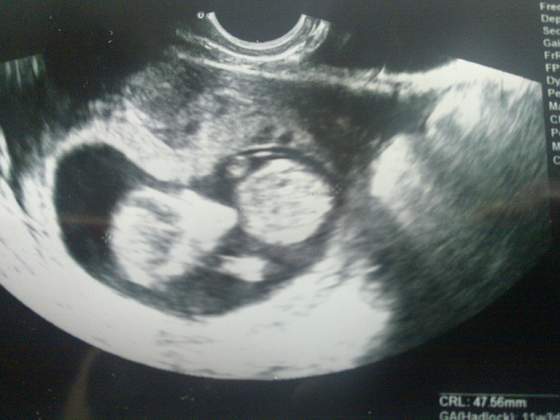

Tak jak obiecałam, dodaje fotki korniczka w wieku 9 tygodni :-)

Załączniki

• 1.jpg

1.jpg

13,5 KB · Wyświetleń: 102